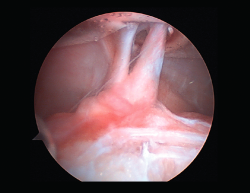

Rigidez

Una de las complicaciones más temidas, producida por un aumento del tejido fibroso, ya sea por la propia lesión (primaria) o secundaria a diferentes motivos (error técnico en la cirugía, síndrome del cíclope, inmovilización prolongada o la participación insuficiente en un programa de rehabilitación, infección, síndrome del dolor regional complejo, hematomas o sinovitis) (Figuras 7 y 8). Esta puede variar desde una ligera limitación del rango de movilidad hasta una severa artrofibrosis(21).

Figura 7. Adherencias intraarticulares.